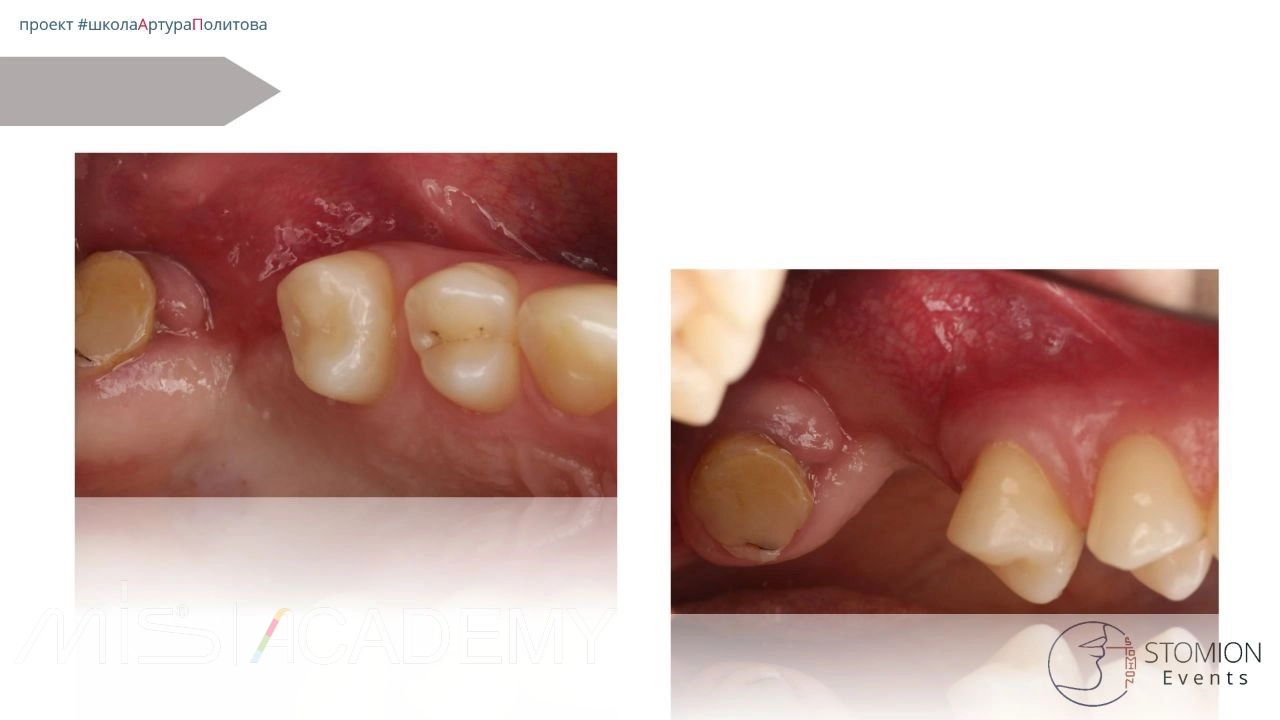

Первичный приём в нашей клинике:

• Сняты швы.

• Проведена проба — отмечена миграция воздуха.

• Назначена асепта на постоянной основе 3 недели.

Контроль через 2 месяца:

• Свища нет.